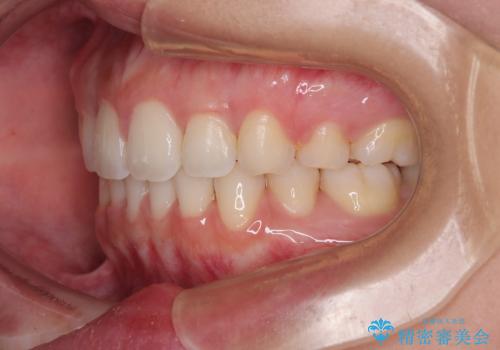

- 全体的なデコボコと口元の突出感を改善したいとのことで来院された患者様です。

このままデコボコを整えるとさらに突出感が増すため、上下左右の第一小臼歯を抜歯し、ワイヤー装置にて矯正しました。

結婚式で途中装置を外した時期がありましたが、2年で治療を終えることができました。